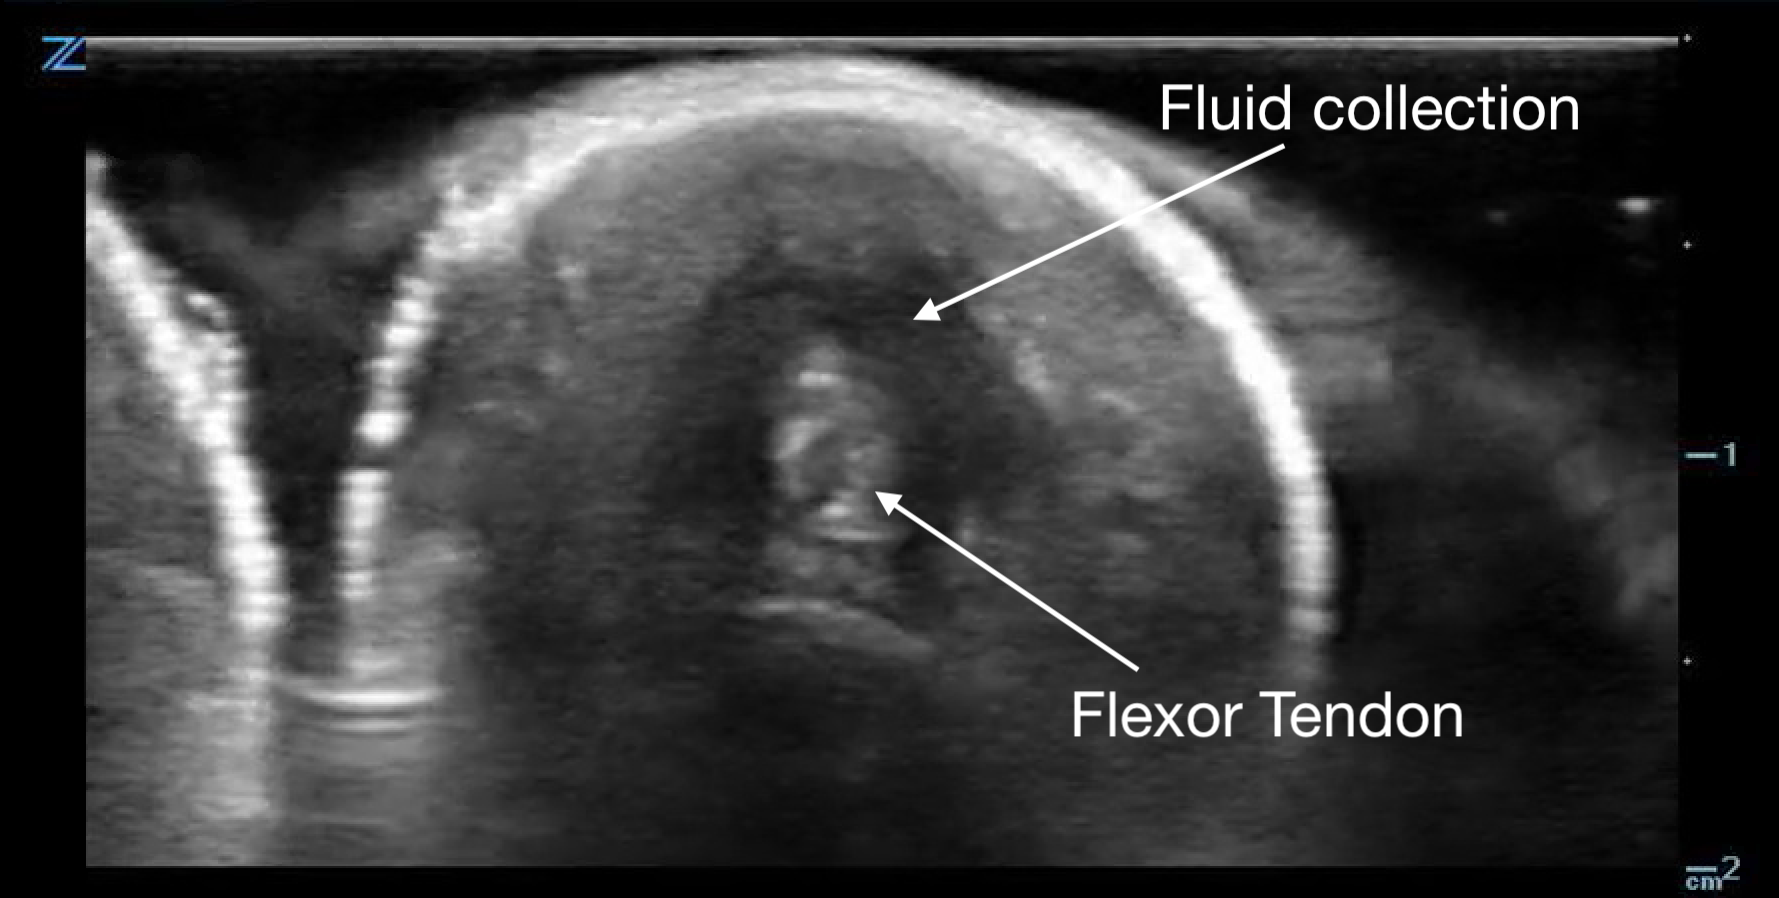

Tenosynovitis will appear as a thickened tendon and on short axis will have a halo of anechoic fluid surrounding it in the tendon sheath.

Figure 14a.

Flexor tenosynovitis demonstrated by the halo of fluid in the sheath surrounding the tendon

Figure 14b.

a long axis view with fluid above and below the flexor tendon.